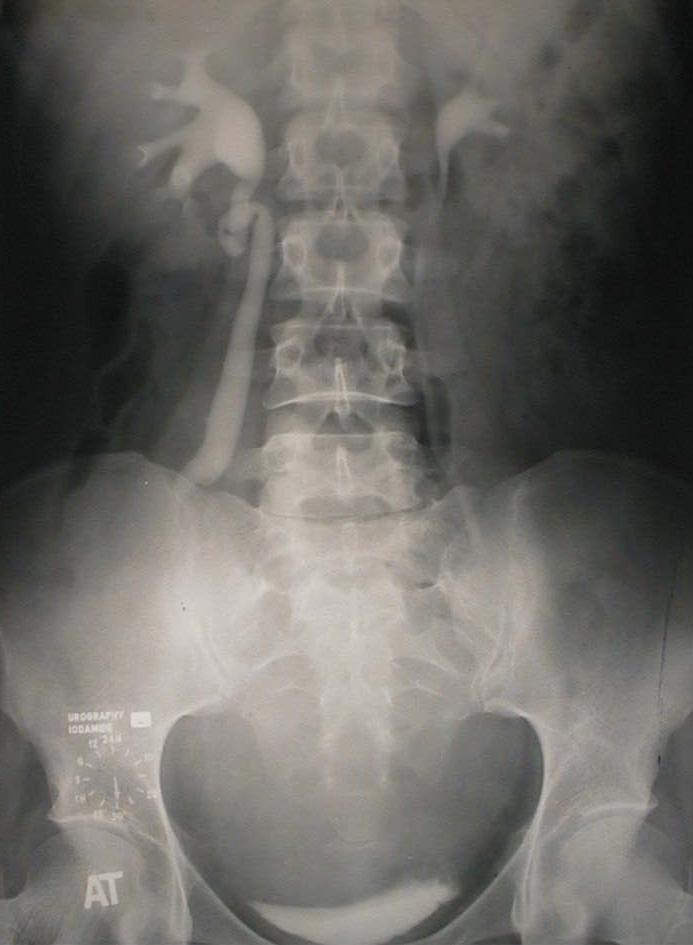

Urography: right hydroureteronefrosis, interruption of the opacity of the ureter at the iliac crest level. Latero deviation and compression of the left ureter. Compression of the bllader.

Urografie: hidroureteronefroză dreaptă, cu întreruperea ureterului la nivelul crestei iliace.

Deviere laterală și compresiune a ureterului stâng. Amprentă de compresiune asupra vezicii urinare.